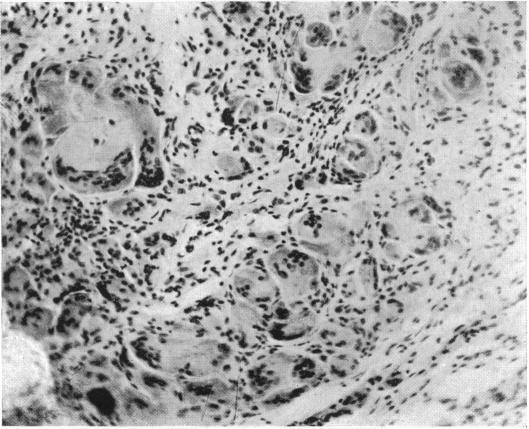

BENIGN XANTHIC EXTRAPERIOSTEAL TUMOR OF THE EXTREMITIES CONTAINING FOREIGN BODY GIANT CELLS.

Ann Surg. 1919 Nov;70(5):574-81. doi: 10.1097/00000658-191911000-00011.